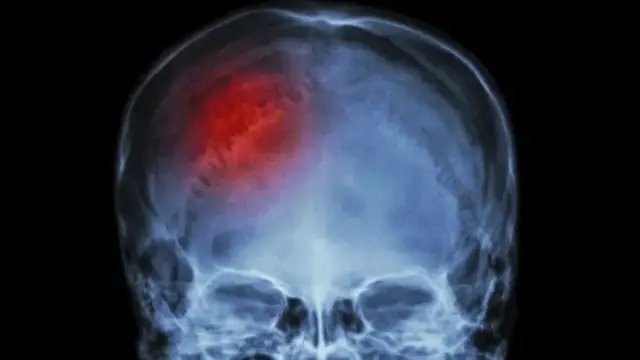

Istaroogga ayaa ah xanuun ku dhufta maskaxda kaas oo u kala qeybsama labo qeybood oo kala ah in maskaxda uu dhiig ku furmo iyo nooca kale ee ah in dhiigga uu ka xirmo maskaxda.

Nooca dunida ugu badan ayaana ah marka maskaxda uu dhiiggu ka xirmo waana 85% guud ahaan caalamka.

Faaligga ayaa ah xaalad aad u halis badan oo qofka noloshiisa baddaleysa, taas oo qofka ku keeneysa in uu curyaamo ama in uu dhinto. Calaamadaha lagu arko ayaana kamid ah in qofka uu hadalka ku xirmo, in lug iyo gacan ay dhacdo oo ay ka lumaan awoodihiisa, qallooc ku yimaada dhanka wajiga iyo in qofka isaga oo aan la fileyn uu koomo galo amaba dhinto.